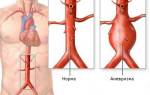

Развитие заболевания зависит от степени поражения аорты и ее подвздошных ветвей. Со временем нижние конечности и внутренние органы, находящиеся в области таза, начинают получать все меньше крови, кислорода и питательных веществ. Участки выше сужения перегружаются, а в нижних конечностях постепенно развивается кислородное голодание, известное как ишемия.

Чем ниже расположено поражение аорты, тем меньше изменяется ее просвет, что способствует лучшему восстановлению кровообращения и упрощает процесс лечения.

Синдром Лериша — нарушение притока крови к органам малого таза и нижних конечностей. Прогрессирование заболевания может привести к серьезным осложнениям, включая гангрену, необходимость ампутации конечности или привести к летальному исходу.